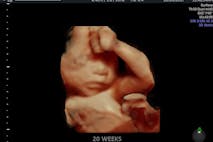

Have you ever wanted to share the miracle of human development with little ones? Live Action is proud to present the "Baby Olivia" board book, which presents the content of Live Action's "Baby Olivia" fetal development video in a fun, new format. It's perfect for helping little minds understand the complex and beautiful process of human development in the womb.